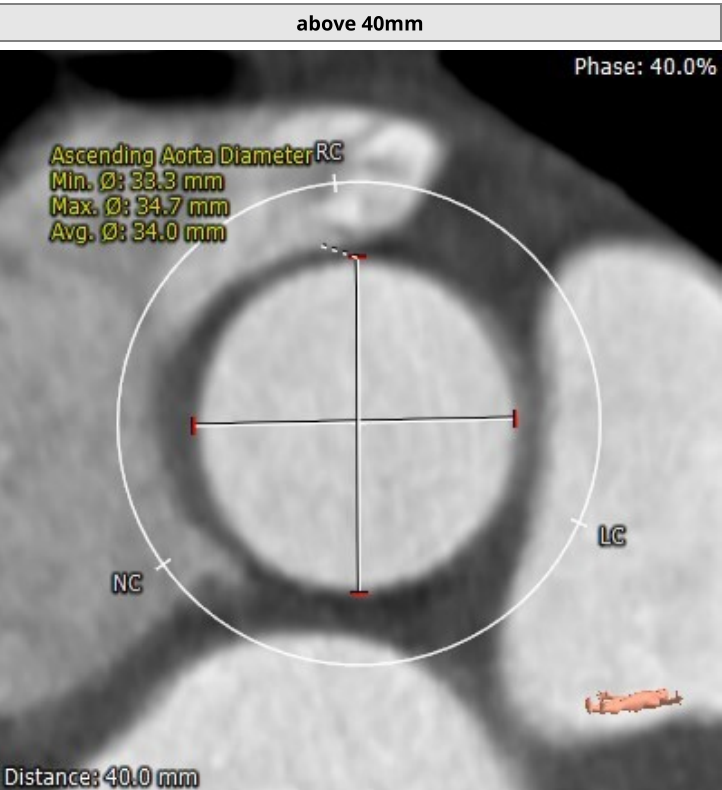

该名患者为三叶瓣,右冠窦轻度钙化。瓣环直径为23.2mm,周长为72.9mm。左冠窦中重度钙化。升主动脉稍增宽,平均直径34.0mm。左冠开口高度13.3mm,右冠开口高度15.1mm,冠脉风险低。外周血管钙化轻,入路情况较佳。

升主动脉